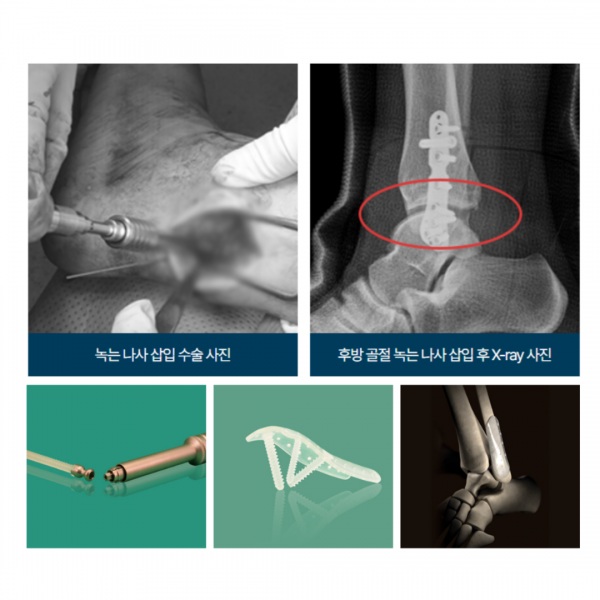

족부센터 발목 골절 녹는 나사 삽입술

서울대 출신 정형외과 전문의 4인이 족부질환을 집중적으로 진료하는 두발로병원에서 발목 골절 녹는 나사 삽입술에 대해 알려드리겠습니다.

녹는 나사는 생체 내에서 자연스럽게 분해되는 특수 재질로 만들어진 고정 기구입니다. 수술 후 약 2년이 지나면 체내에서 녹아 흡수되기 때문에 별도의 제거 수술이 필요하지 않습니다. 두발로병원에서는 핀란드 INION 사에서 제작한 생체 분해성 의료기기를 도입하여, 안전성과 고정력을 동시에 확보한 나사를 사용하고 있습니다.